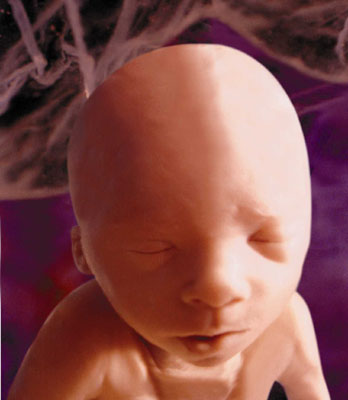

Part of the push to lower the abortion limit was the new ultrasound technology which could produce images like this one, taken at 24 weeks: